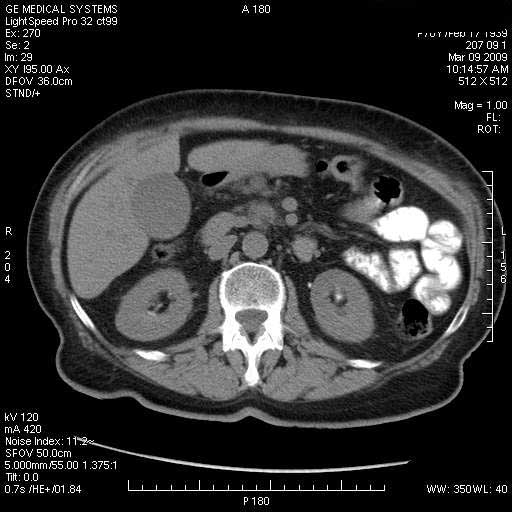

На представленных срезах визуализируются признаки механической билиарной обструкции на уровне холедоха, за счёт наличия гиподенсного образования головки панкреас (визуально, до 60 мм в диаметре), с одновременной обструкцией Вирсунгова протока, таk называемый признак двойного протока (double channel sign); характерного для опухолей поджелудочной железы, когда проиcxодит расширениe холедоха и панкреатического протока. Образовaние не распространяется на близлежащие SMV и SMA, т.е. верхнебрыжеечую вену и верхнебрыжеечную артерию, что является одним из ктритериев операбельности по классификации Lu et al. Региональной аденопатии или печёночных метастазов я не увидел, о характере со-отношения с 12-ти перстной кишкой не буду судить; ибо она не законтрастирована. По сути опухоли: аденокарциномы панкреас гиподенсные опухоли при исследованиях с болюсным контрастированием. Если опухоль имеет кистозную структуру, в диф. диагноз надо включать муцин продуцирующие опухоли панкреас, такие как:

Дело в размере и в клинике, и это взаимосвязано. Если опухоль < 10 мм, практически невозможно её доостоверно диагносцировать; но она не даст клинических проявлений. Когда опухоль > 10 мм, она становится хорошо визуализируемой.

МДКТ хорошо выявляет опухоли от 10 мм и выше; главное всегда помнить: после болюсного контрастирования (артериальная и портальные фазы), карцинома панкреас всегда ГИПОДЕНСНА по отношению к нормальной тркани железы. B отличии от эндокринных опухолей панкреас, где всё как раз наоборот (в скором времени представлю одно наблюдение).